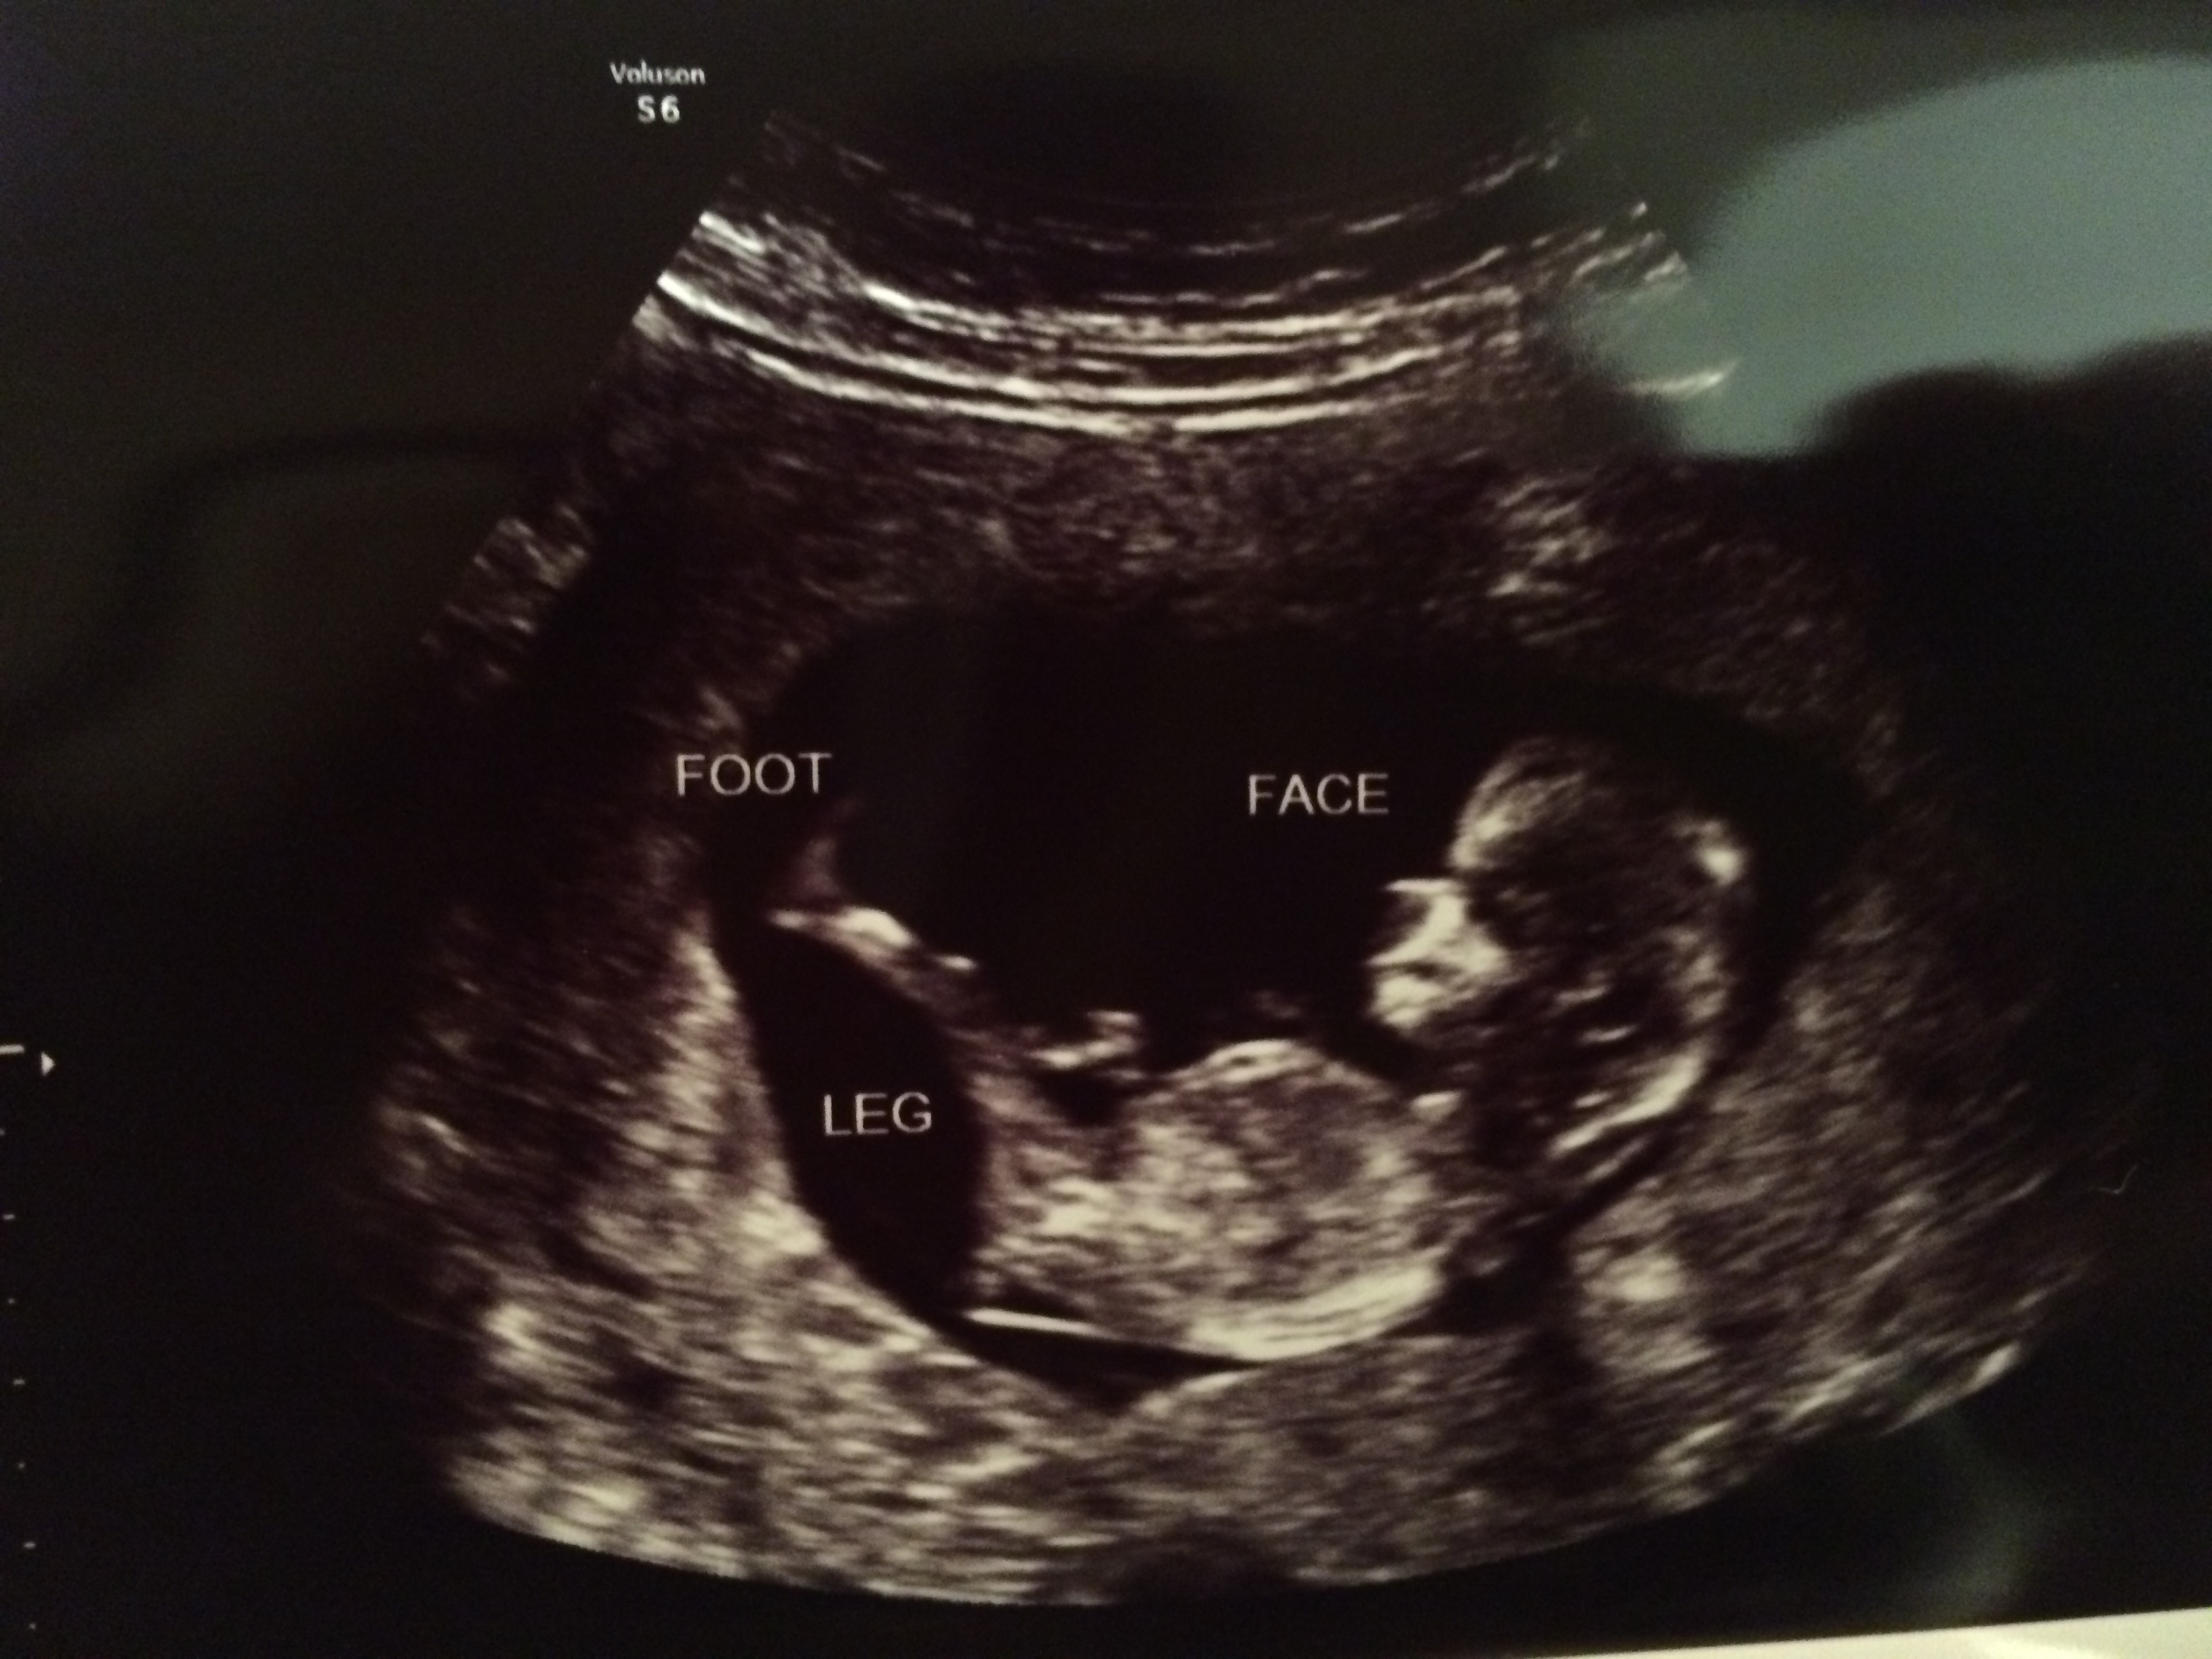

12 wk 1 day Nub and Potty Shots - Please guess Baby #4!

We had our NT scan today and our u/s tech took a guess. The baby measured 12 wk 1 day. This is our 4th baby. The same tech has been our tech every time and she always guesses at the NT scan. She guessed wrong with baby #1, couldn't see with baby #2, and guessed right with baby #3. She took a guess today and I'd like to see what y'all think and if it's in line with her guess. I'll wait to tell you what she said after I get some guesses :) We go back for another u/s at 16 weeks to confirm the sex.

Attachment 24664